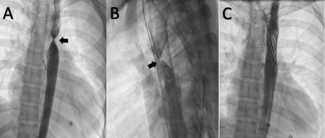

The authors present a 70-year-old man with rheumatic mitral valve disease who had undergone 3 previous open-heart surgeries, the last of which was a new mitral valve replacement for a mechanical prosthesis due to early bioprosthetic...